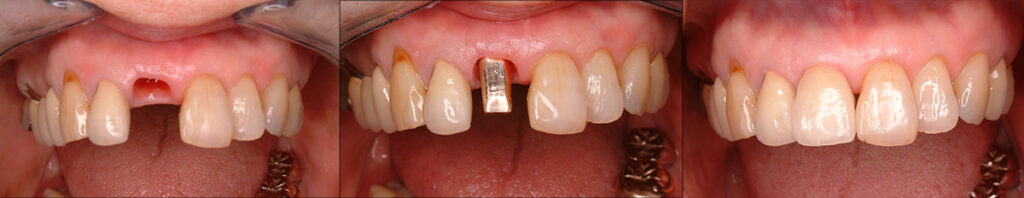

78歳で前歯ハセツ抜歯後インプラントで再建

麻酔をして周辺歯を削ってブリッジとするより却って侵襲がすくない治療となりました

70代半ばで前歯崩壊をインプラントで再修復

下顎に広範囲のインプラント治療が施され快適に過ごされていたので、上顎前方部の歯質劣化により残存歯でのブリッジが不能のためインプラント修復をご希望

義歯を使われることなく12年使用され、90歳手前で急に衰えられご逝去されました。